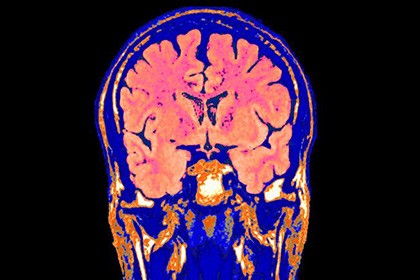

Amerikanın "Bioquark" şirkəti ölü insan beyninin

canlandırılmasının mümkün olduğunu sübut etməyi

planlaşdırır.

Publika.az xəbər verir ki, şirkət insan

orqanizminin əsas orqanının canlandırılması üçün texnologiyaları

hazırlamaq niyyətindədir. Sözügedən ideya ilə şirkətin rəhbəri Ayra

Pastor çıxış edib.